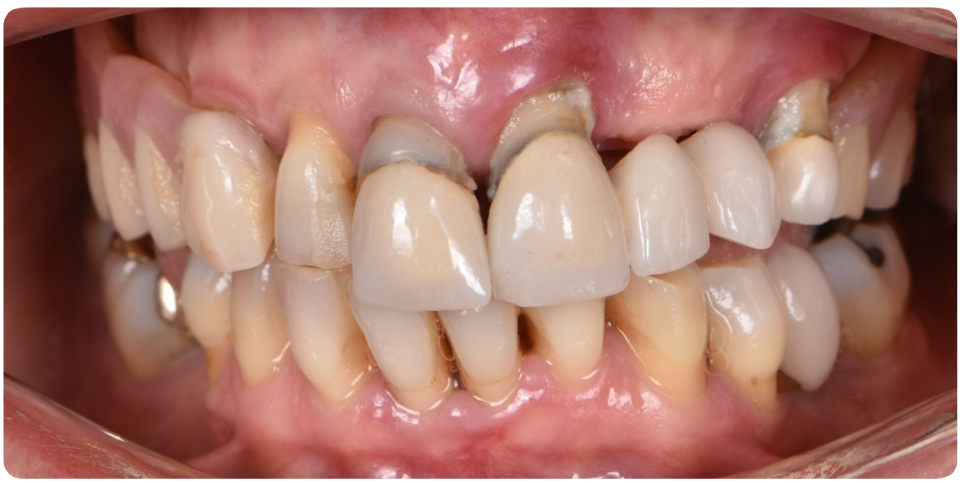

Complex Implant Rehabilitation

Complex dental implant rehabilitation is a highly effective solution for patients with extensive dental issues.

Such as severe bone loss, multiple missing teeth, cases involving tumor resection and reconstruction with vasculised bone grafts, gun shot injuries, with cleft lip and palate, jaw necrosis, post cancer oral rehabilitation.

Treatment plan includes Detailed clinical and radiographic evaluation of the patient’s general and oral health, including gum condition, remaining teeth, and bone structure with 3D scans, X-rays, and CT scans.